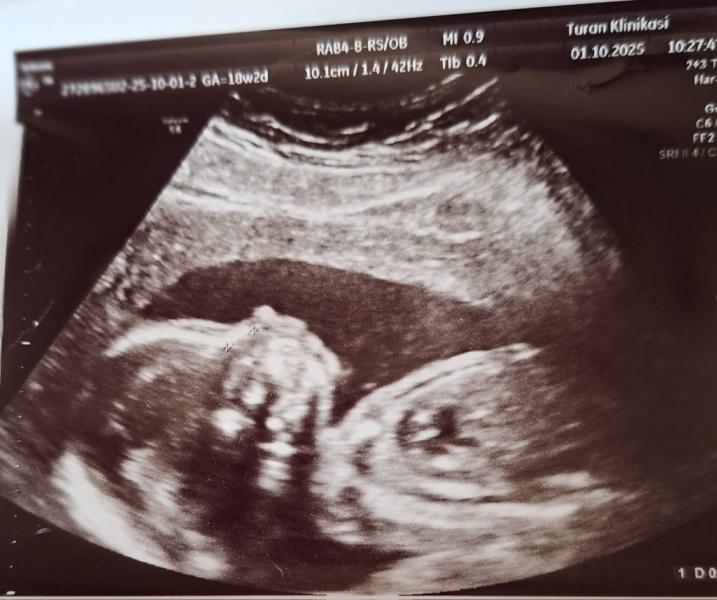

Devocki moyemu scastyu net pridela bila segodna na 2m skrininge wukur vse xorowo.

Aa da u menya budet devocka)ya bezumno scastliva🥰